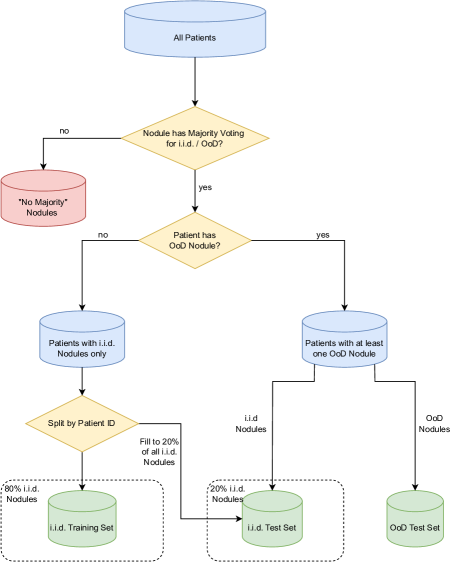

LIDC-IDRI (LIDC) To study uncertainty methods in a real-world setting, we use the LIDC-IDRI dataset (Armato III et al. (2011)), with the task to segment long nodules in 64x64x64 crops from 3D CT volumes, similarly to Kohl et al. (2018). We only include nodules that have been annotated by four different raters serving as an AU reference. We further induce EU by designing two distribution shifts based on two metadata features, which are textured (i.i.d) vs. non-textured (OoD) (texture shift/ LIDC TEX) and benign (i.i.d) vs. malignant (OoD) nodules (malignancy shift/ LIDC MAL).

Next, we construct a train/test split to analyze the performance difference of a deterministic U-Net model on the i.i.d. test set and the OoD test set. The way this split is constructed is shown in Figure 6. We first remove all nodules that do not have a majority vote for being i.i.d. or OoD, i.e. when two raters voted for the nodule being i.i.d. and two voted for the nodule being OoD. Next, all patients are identified that have at least one OoD nodule. The OoD nodules of these patients are added to the OoD test set and the i.i.d. nodules of these patients are added to the i.i.d. test set. From the remaining patients that only have i.i.d. nodules, most of the nodules are taken in the i.i.d. training set and some nodules are added to the i.i.d. test set, such that the overall ratio of i.i.d. nodules in the training set and the i.i.d. test set is . The split which cases to include in the training set and the i.i.d. test set is decided by the patient identifier. With the described approach for creating the splits, it is ensured that no patient has nodules in the training- and the test set at the same time.